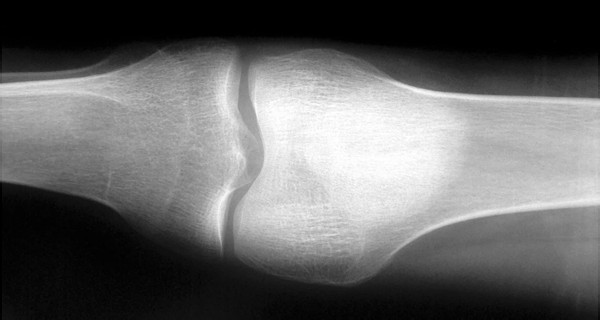

Медицинские снимки: рентген коленного сустава при остеопорозе